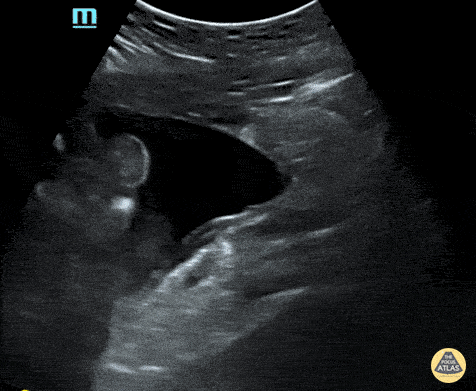

Sagittal view of the pelvis showing free fluid. Contributor: Maher M. Abulfaraj, MD, @mahermabulfaraj